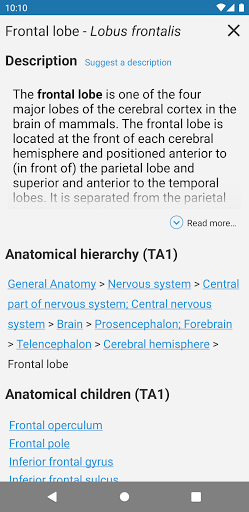

e-Anatomy memiliki lebih dari 26.000 gambar yang berisi serangkaian gambar dalam tampilan aksial, koronal, dan sagital serta radiografi, angiografi, gambar diseksi, bagan anatomi, dan ilustrasi. Semua gambar medis diberi label dengan cermat, lebih dari 967.000 label tersedia dalam 12 bahasa termasuk Terminologia Anatomica Latin.

- Ketuk label untuk menampilkan struktur anatomi

Bahasa Indonesia : * Memperkenalkan tabel dalam definisi struktur anatomi untuk penataan data yang lebih baik